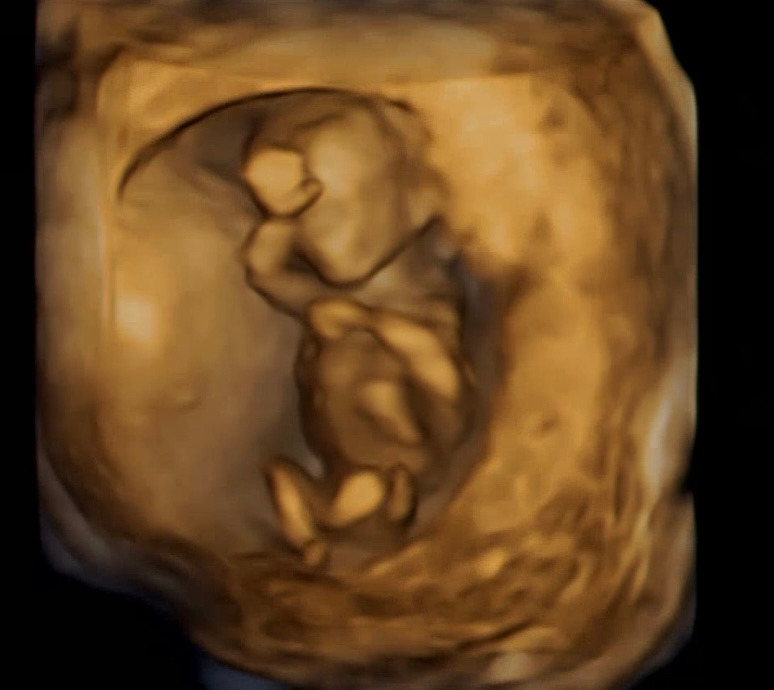

오늘은 오전에 여유롭게 병원을 들렸고, 지난번 어지러움에 대해 의사선생님과 가벼운 이야기를 나눴다. 어지러우면 머리를 감싸쥐고 앉는게 방법이라는데, 내가 옆에 없을때 할 수 있는 선택지가 그것뿐이라니 안심보다는 걱정이 앞섰다. 그런 걱정이 무색하게, 겨울이는 오늘 손을 번쩍 들어주었다. 아내가 낮잠을 잘 때 자세와 너무나 비슷해서 온 가족(겨울이 이모)이 같은 사진을 찾느라 하루를 다 보냈다. 심장도 여전히 세차게 뛰고 있었고, 벌써 6cm까지 키가 컸고, 몸을 조금 꿈틀거리기도 했다. 그리고 초음파상으로 기형아 걱정은 없다고 하셨다. 우리의 걱정과 다르게 겨울이는 하루하루 잘 크고 있다. 다음 병원을 갈 때면, 겨울이의 성별을 알 수 있고, 겨울이가 건강하게 태어날지도 어느정도는 알아볼 수 있다.

12주 3일.jpg